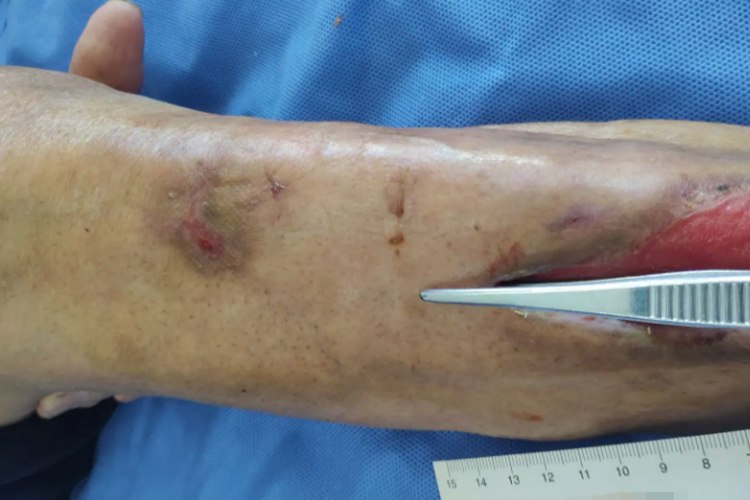

窦道:是指伤口局部出现的异常脓肿通道或腺腔,而且损害周围常出现软组织红肿,触之有弹性及波动感,中央凹陷有窦孔可见,并排出脓液。

如果伤口出现潜行或窦道,需及时遵医嘱采取相关治疗,可选择清创术,规范地进行清洗去污、麻醉、清创、缝合、引流、包扎。需选择合适的敷料,比如水凝胶敷料、藻酸盐敷料、水胶体敷料等。也可由医生进行择刮、部分肉芽清除等方法处理,同时定期换药,以促进伤口愈合。